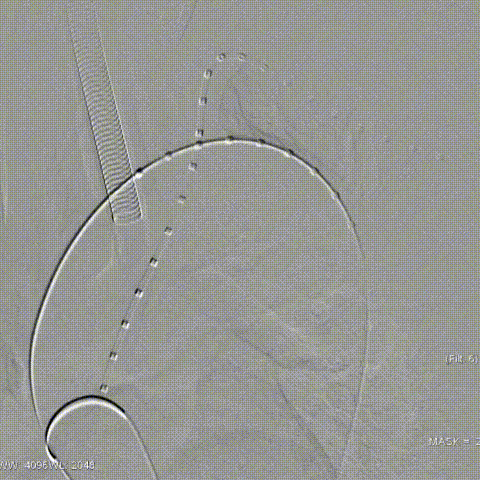

★ 术后造影

支架释放完毕后,分别进行左前斜和右前斜造影。结果显示,支架形态良好,左侧颈总动脉和左锁骨下动脉分支血流通畅。右前斜位可见假性动脉瘤封闭完全,仅有少量内漏,考虑与膜渗相关。同时行颅内动脉造影,结果显示双侧颈动脉、双侧椎动脉以及颅内血管显影良好。结果表明,手术成功实现血管重建,假性动脉瘤有效封堵,且未对脑部供血造成不良影响。